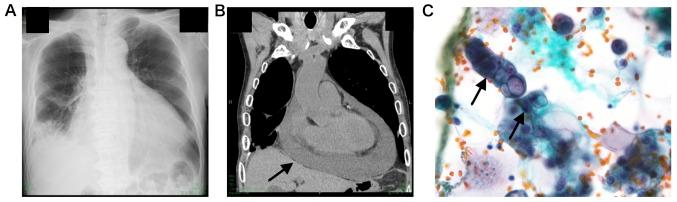

Recent therapeutic advancements have prolonged the survival duration of patients with metastatic or recurrent colorectal cancer even during salvage treatment. Although treatment with regorafenib and trifluridine/tipiracil combination has exhibited apparent survival benefits, clear and objective evidence of a response to these drugs is scarce. Herein, the present study reports the case of a patient with rectal cancer refractory to multiple surgical interventions and standard chemotherapy. Treatment with regorafenib resulted in immediate improvement of respiratory failure caused by pulmonary lymphangitic carcinomatosis. This improvement persisted for over 3 months and was confirmed by radiology. Our findings suggest that regorafenib can reduce peritumoral edema via its interaction with the vascular endothelial growth factor receptor. Thus, regorafenib functions as a multityrosine kinase inhibitor to alleviate symptoms of lymphangitic carcinomatosis despite the low potency of the drug.

近期的治疗进展延长了转移性或复发性结直肠癌患者的生存期,即使在挽救治疗期间也是如此。尽管瑞戈非尼和曲氟尿苷/替匹嘧啶联合治疗已显示出明显的生存获益,但关于这些药物反应的明确客观证据却很少。在此,本研究报告了一例直肠癌患者,该患者对多种手术干预和标准化疗均耐药。瑞戈非尼治疗使由肺淋巴管癌病引起的呼吸衰竭立即得到改善。这种改善持续了3个多月,并得到了放射学证实。我们的研究结果表明,瑞戈非尼可通过与血管内皮生长因子受体相互作用来减轻肿瘤周围水肿。因此,尽管瑞戈非尼药效较低,但它作为一种多酪氨酸激酶抑制剂可缓解淋巴管癌病的症状。